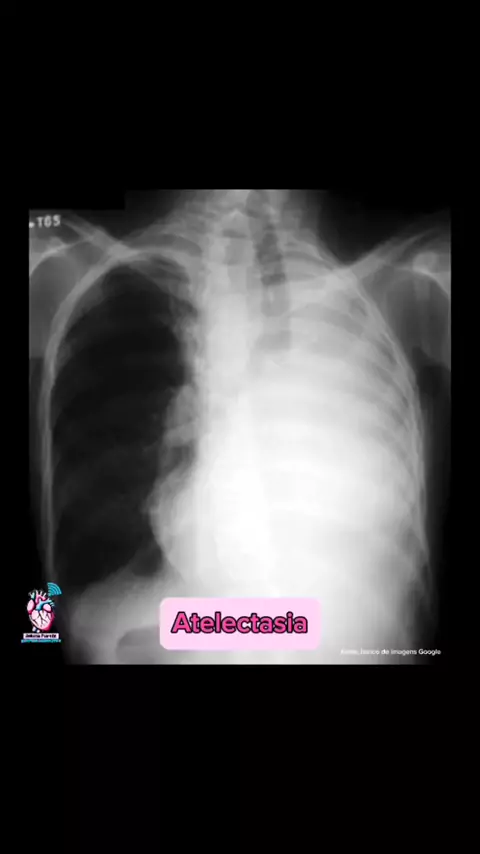

Radiografia de algumas patologias. E sempre bom, bater o olho e já ter uma base do que seja… os casos clínicos. #criadordeconteu #enfermagemporamor #dpoc #pulmao #viralizaaah